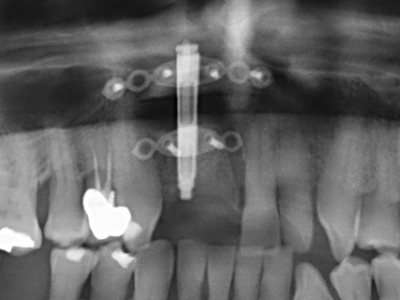

Si es preciso realizar intervenciones quirúrgicas en las que el hueso está en contacto directo con estructuras sensibles, como son los vasos sanguíneos o los nervios, los instrumentos rotativos presentan un enorme potencial de provocar lesiones iatrogénicas. Así, precisamente en la representación de nervios después de una lesión iatrogénica, o en el transcurso de la lateralización de un nervio para resecciones, reconstrucciones o incorporación de implantes, los equipos piezoeléctricos pueden resultar muy útiles para preparar la tapa ósea y retirar las partes de tejido duro cercanas al nervio (fig. 17-20). Por lo general, un ligero contacto del cordón nervioso con el inserto piezoeléctrico no tiene consecuencia alguna; ahora bien, un procedimiento poco cuidadoso con movimientos tipo sierra o piezas de trabajo sobre la base ósea aún existente puede provocar lesiones nerviosas temporales o incluso permanentes. Con todo, el riesgo de sufrir una lesión de este tipo se considera significativamente inferior que en los casos en los que se utilizan sierras y fresas (Pereira, Gealh et al. 2014).

Aplicación: Terapia periodontal

Para la extracción de implantes es posible realizar la preparación de una tapa ósea vestibular que, tras retirar el tornillo del implante, vuelve a fijarse y, de este modo, mantiene el contorno de la apófisis alveolar.

En la cirugía del seno maxilar surgen otros campos de aplicación: En este punto, tras la preparación concéntrica de una tapa ósea de la pared del seno maxilar (que suele tener forma trapezoidal), es posible eliminar patologías y cuerpos extraños del seno maxilar. La tapa ósea se repone después de finalizar la parte intra-antral de la operación y se asegura frente a una posible dislocación mediante cuñas o suturas adaptables.